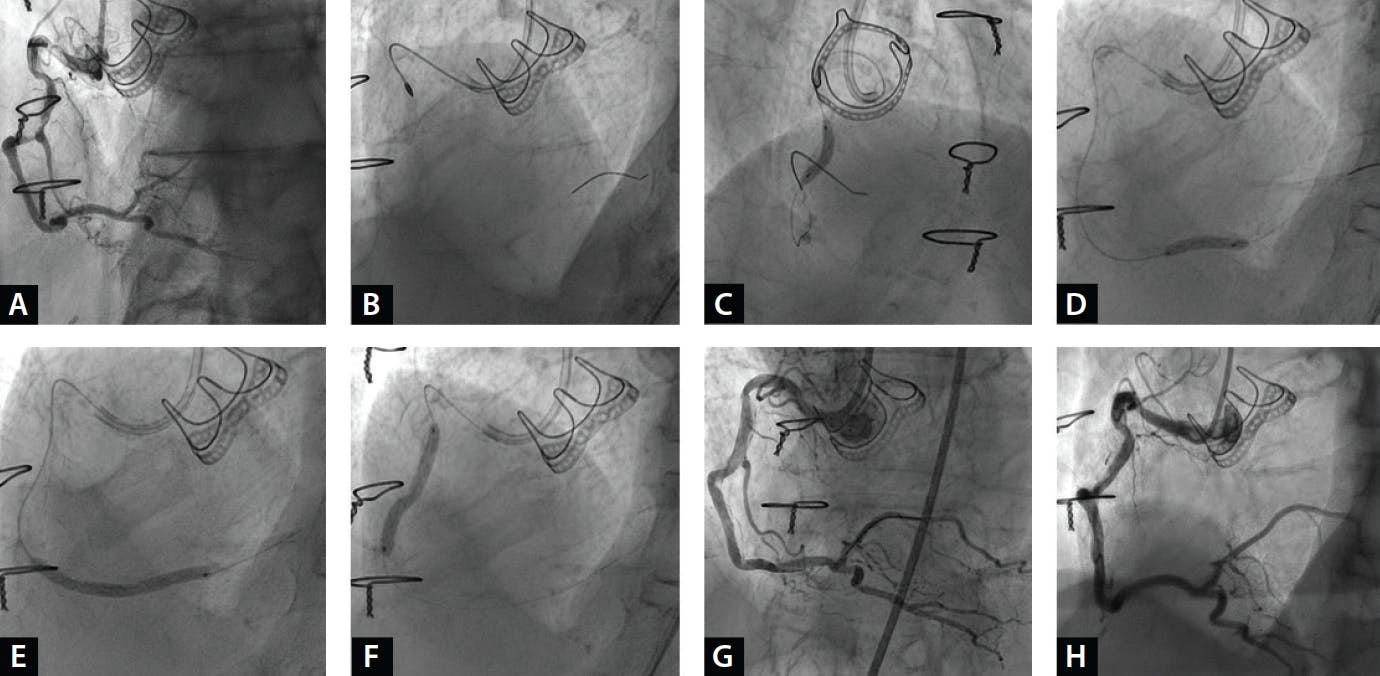

Figure 2. DCB angioplasty in a tortuous right coronary artery. Calcific lesions at the midproximal and distal segments of a tortuous diffusely diseased right coronary artery (A). Lesion preparation included rotational atherectomy with a 1.5-mm burr at the midproximal segment (B) and high-pressure, 3.5-mm NC balloon angioplasty along the vessel (C, D). Angioplasty with two sirolimus-coated 3.5- X 30-mm DCBs followed (E, F). Final angiography showed an adequate and stable result, with non–flow-limiting dissections at both segments (G). Spontaneous dissection healing and preserved lumen gain were evident at 1-month follow-up angiography (H).